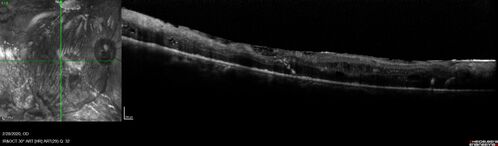

Severe diabetic tractional retinal detachment one year following diagnosis of type II Diabetes Mellitus

44 year old man The vision in the left eye started to decline about 4 days ago.  Prior to that the left eye was the better eye.  He was diagnosed with diabetes a year ago.

VA OD: Dcc20/50-1 OS: Dcc20/125-2, TP: OD:12 OS:13

Following two surgeries in each eye, silicone oil remaining forever, monthly anti-VEGF for severe DME - BCVA OU 20/200 at 3 years